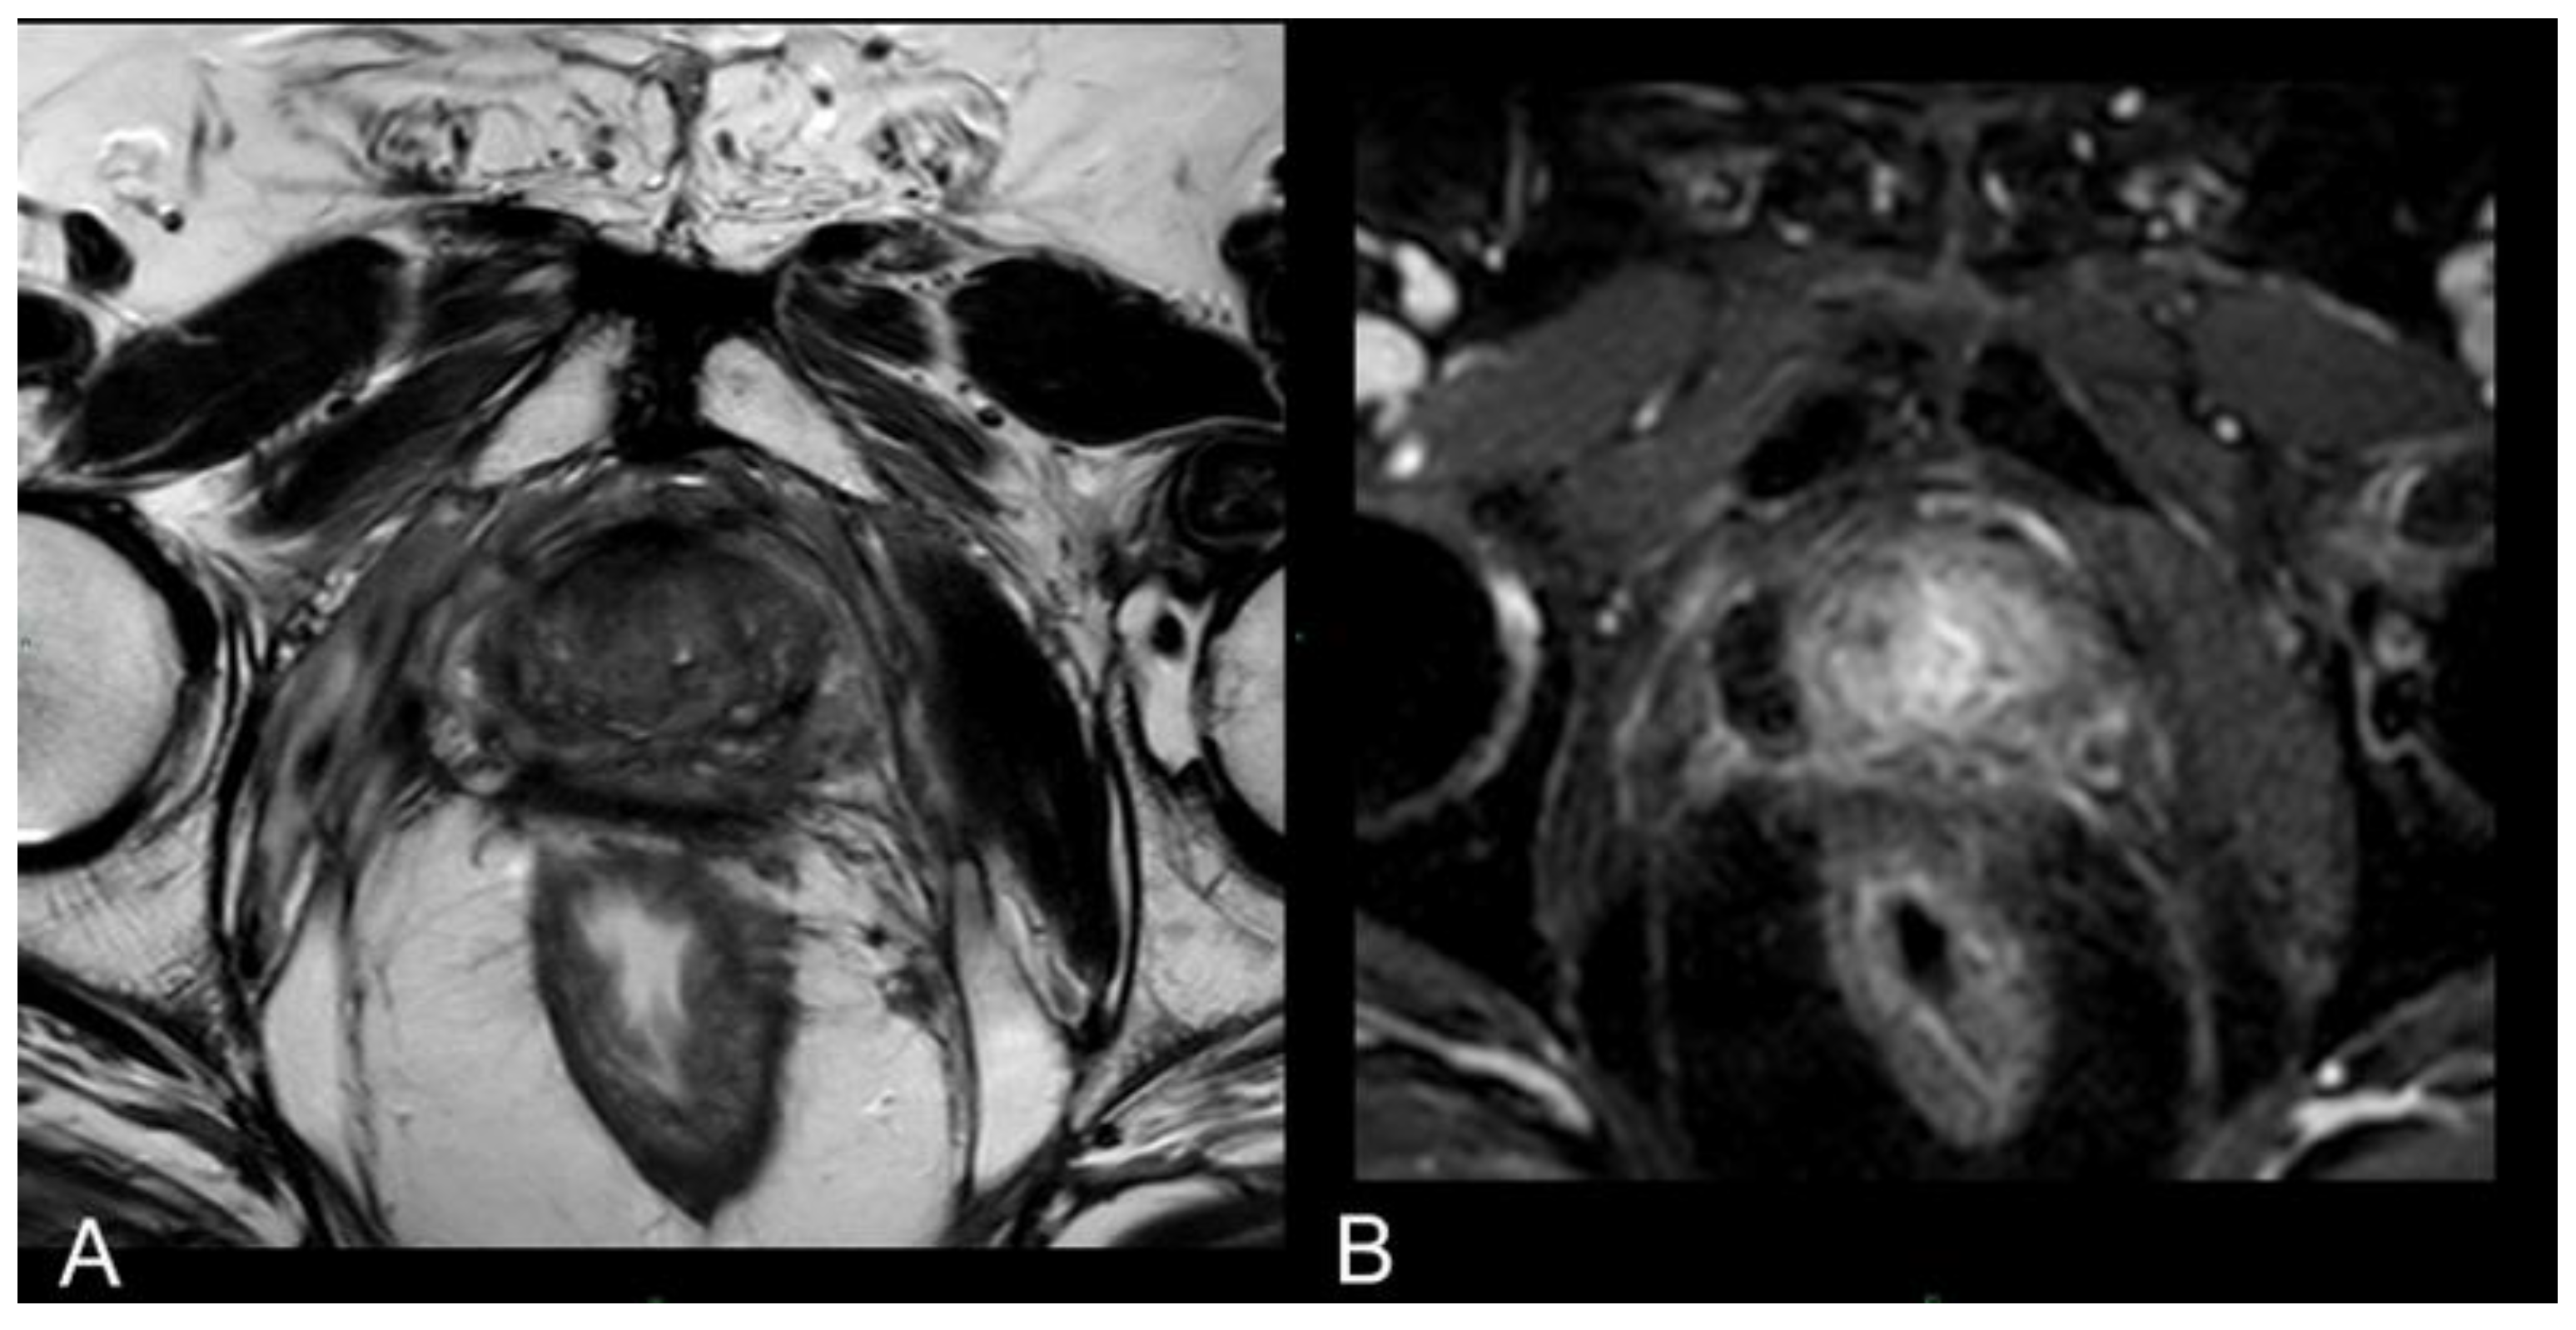

Immediate post-treatment mpMRI examinations consistently revealed the presence of a devascularized ablation cavity characterized by coagulative necrosis in all cases, and notably, this cavity exhibited a volume approximately three times larger than the original cancer lesion (as illustrated in Figure 2).

Immediately following the procedure we observed elliptical hypointense ablation cavities, roughly three times the size of the original lesions. Some of these cavities contained fluid and/or complex fluid (comprising blood and proteinaceous material), with hyperintense fiber tracks discernible within the treated area (as depicted in Figure 2a, b).

At 1 month - 6 months - 12 months: the main findings included the laser fiber tracks surrounded by a large elliptical-shaped necrotic tissue cavitation, which appeared hypointense on T2-weighted images (Figure 2 c, d; Figure 3).

Figure 2. (a) T2-w TSE sequence on axial plane 1-hour after the treatment: An elliptical ablation cavity superimposing the lesion, filled with blood derivates and fluid as a result of tissue ablation. (b) DCE T1-w Dixon sequence 1-hour after the treatment: non enhancing cavity in the right peripheral zone. (c) T2-w sequence on axial plane at 1-months follow-up: much wider ablative lesion with core charring, a hyperintense thick rim of necrotic tissue with an outer hypointense thin rim of hemorrhage. Fiber tracks are visible as hyperintense spots. Bulging of the capsule and liponecrosis on the right recto-prostatic triangle. (d) DCE T1-w Dixon sequence on axial plane at 1-months follow-up: unenhancing ablation cavity with a thick margin.